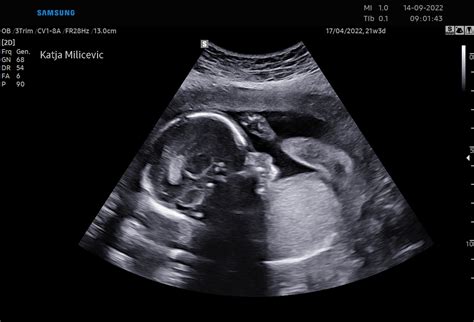

Če boste imeli ultrazvočno preiskavo sedaj, bo ginekolog pogledal plodovo lego in ga izmeril. Preveril pa bo tudi, koliko imate plodovnice in kakšno je stanje posteljice. Morda pa vam bo izmeril še pretok krvi skozi popkovnico in preštel dihalne gibe ploda.

Če bi se rodil sedaj, najbrž že ne bi imel več večjih težav z dihanjem, s sesanjem in z ohranjanjem telesne temperature. Če boste imeli ultrazvočno preiskavo sedaj, bo ginekolog pogledal plodovo lego in ga izmeril. Preveril pa bo tudi, koliko imate plodovnice in kakšno je stanje posteljice. Morda pa vam bo izmeril še pretok krvi skozi popkovnico in preštel dihalne gibe ploda.